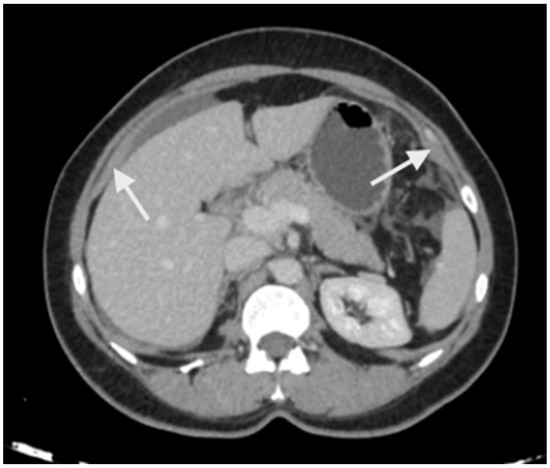

5. Preoperative Imaging